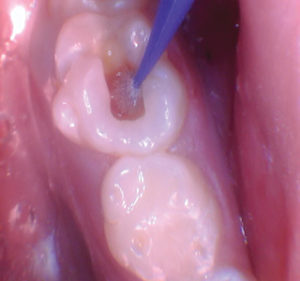

Figura 2. La exposición pulpar se produjo al excavar la dentina infectada (la exposición pulpar no se capturó en la foto). |

Figura 3. Después de quitar el techo de la cámara pulpar. |

Figura 4. Después de excavar el tejido pulpar en los orificios del canal, se utilizó una prenda de algodón seco para evaluar la salud de la pulpa mediante la aplicación de hemostasia por presión. |